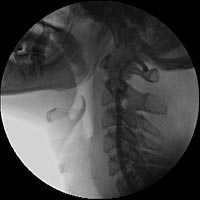

С целью уточнения особенностей кровоснабжения опухоли, а также решения вопроса о возможной эмболизации питающих опухоль сосудов была выполнена ангиография дуги аорты и брахиоцефальных артерий. При ангиографическом исследовании было выявлено слабо васкуляризованное образование, вызывающее перегиб левой внутренней сонной артерии в первом сегменте (рис.3).

Учитывая отсутствие крупных питающих опухоль сосудов, селективная эмболизация не выполнялась.

Рис. 3. Ангиография дуги аорты и брахиоцефальных артерий